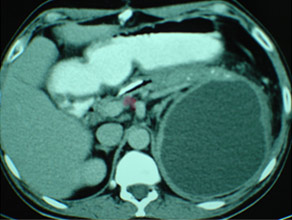

CT scan of pancreatic cancer in the body